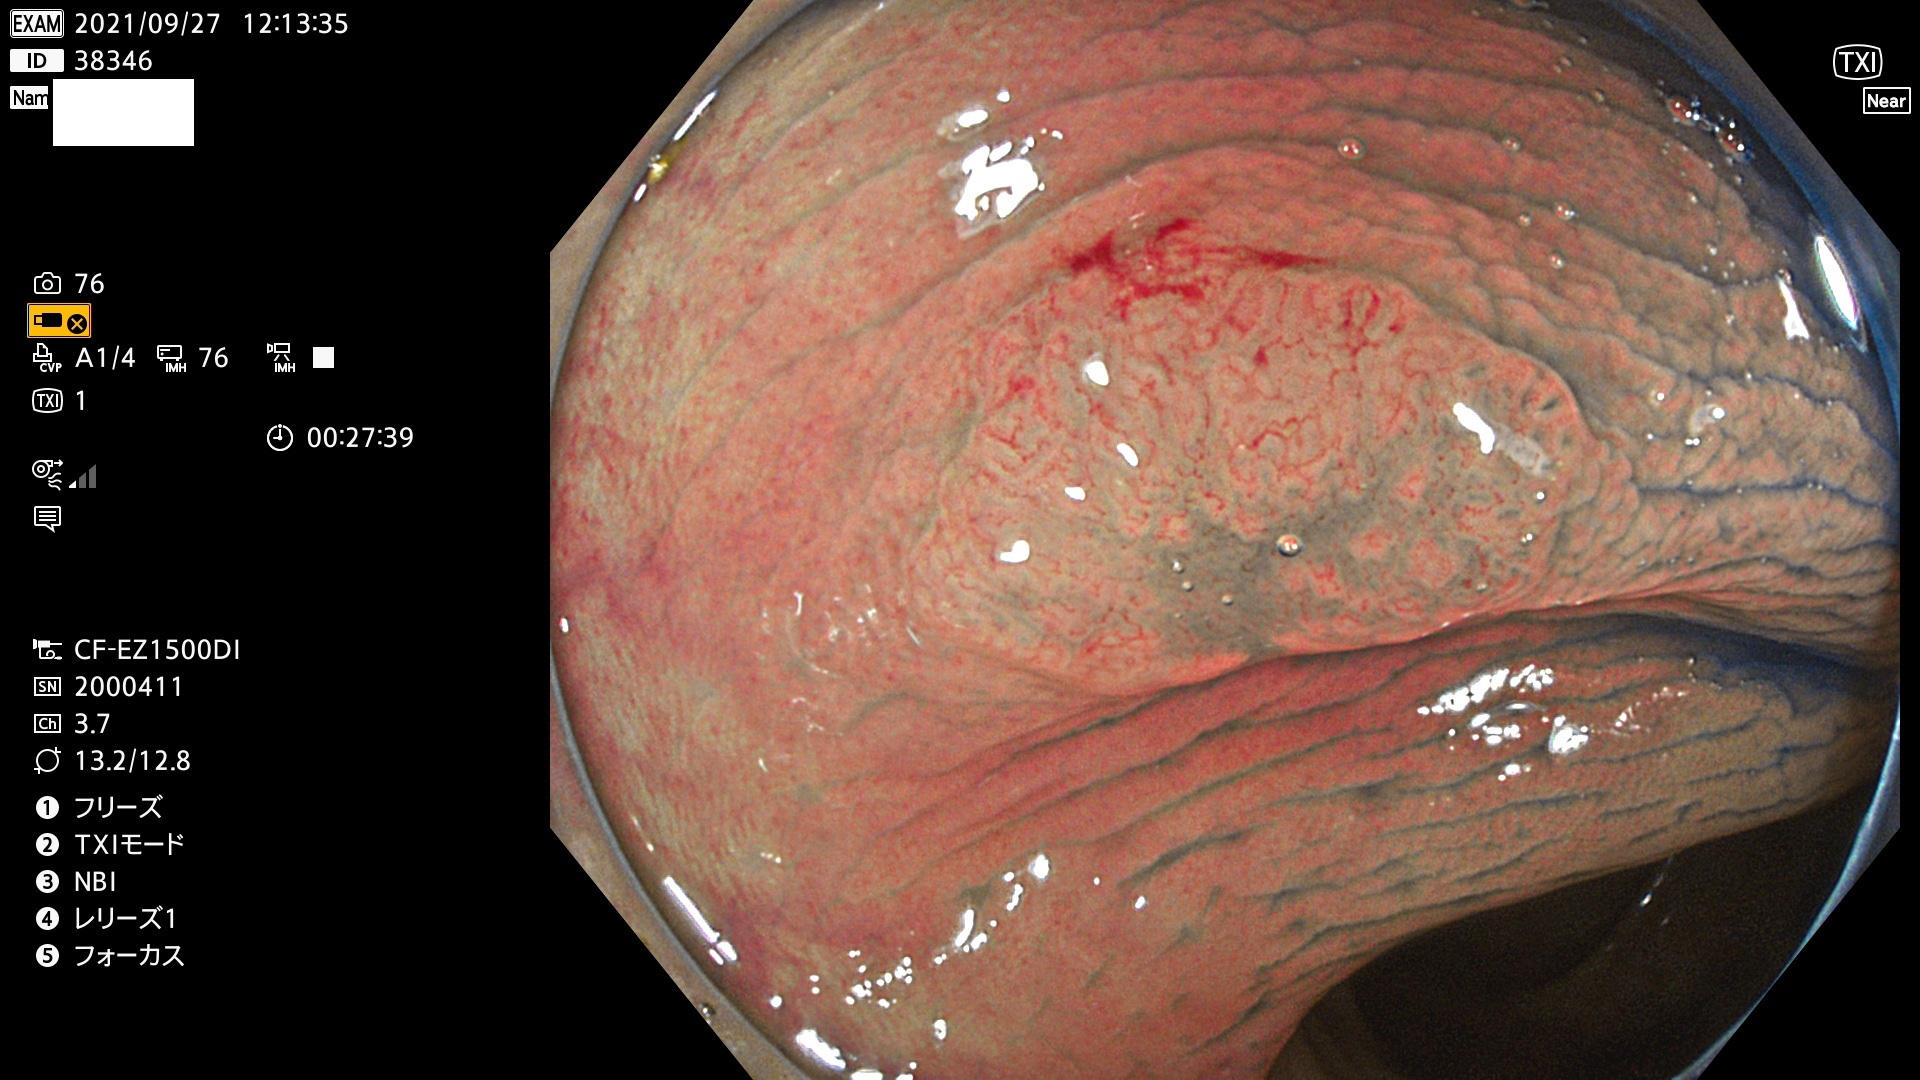

38300 38301 38302 38303 38304 38306 38307 38308 38309 38310 38311 38312 38313 38314 38315 38316 38317 38319 38321 38322 38323 38324 38325 38327 38331 38332 38333 38334 38337 38338 38339 38340 38341 38343 38346 38348 38349 38350 38351 38352 38353 38354 38355 38358 38359 38360 38361 38362 38363 38365 38366(SSAP) 38368 38369 38370 38371(SSAP) 38372 38374 38375 38376 38377 38378 38380 38381 38382 38383 38384 38385 38386 38388 38389 38391(SSAP) 38395 38397 38399

発見困難で危険性の高い平坦型病変(上記100名より抽出)